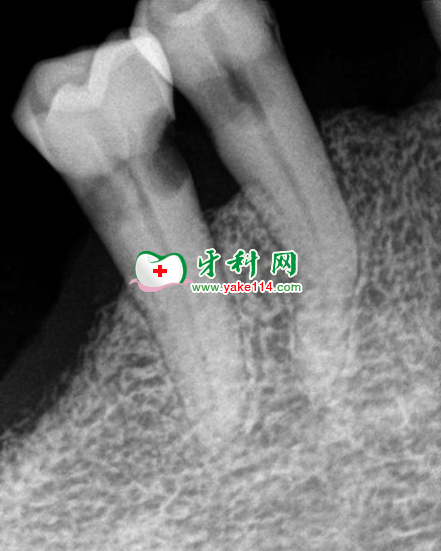

檢查:右下后牙區(qū)僅存第一第二前磨牙,牙周尚可,右下第二前磨牙頰側(cè)及近中頸部可見缺損,呈凹坑狀,深約3mm,未見穿隨,窩洞探痛,無叩痛,無松動(dòng),冷熱刺激敏感。X線示,牙體頸部缺損,缺損去距髓腔約0.5mm。術(shù)前血壓常規(guī)檢查:130/85mmHg。

診斷:1,急性牙髓炎。2,楔狀缺損。

治療:根管治療術(shù)+復(fù)雜充填術(shù)。